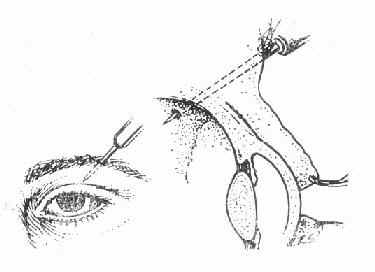

通常找穿孔部位,将眼球穿孔伤分为角膜穿孔伤、角巩膜穿孔伤和巩膜穿孔伤三类。每种可因致伤物的大小、形态、性质、穿入眼球的深度和部位造成多种组织损伤(图15-13)。

图15-3 a.眉弓部穿透伤引起巩膜和视网膜穿透伤